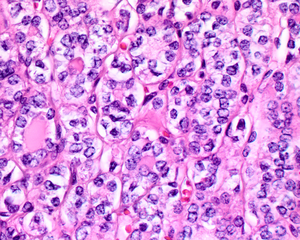

كبسولة ورم الغدة الدرقية NIFTP

لا يوجد دليل على غزو كبسولة النسيج الضام الليفي جيدة التكوين ، مما يساعد على دعم تشخيص NIFTP.

يُظهر ورم NIFTP سمات نووية محددة لسرطان الغدة الدرقية الحليمي.

السمات النووية لسرطان الغدة الدرقية الحليمي ، ولكن داخل ورم مغلف: NIFTP